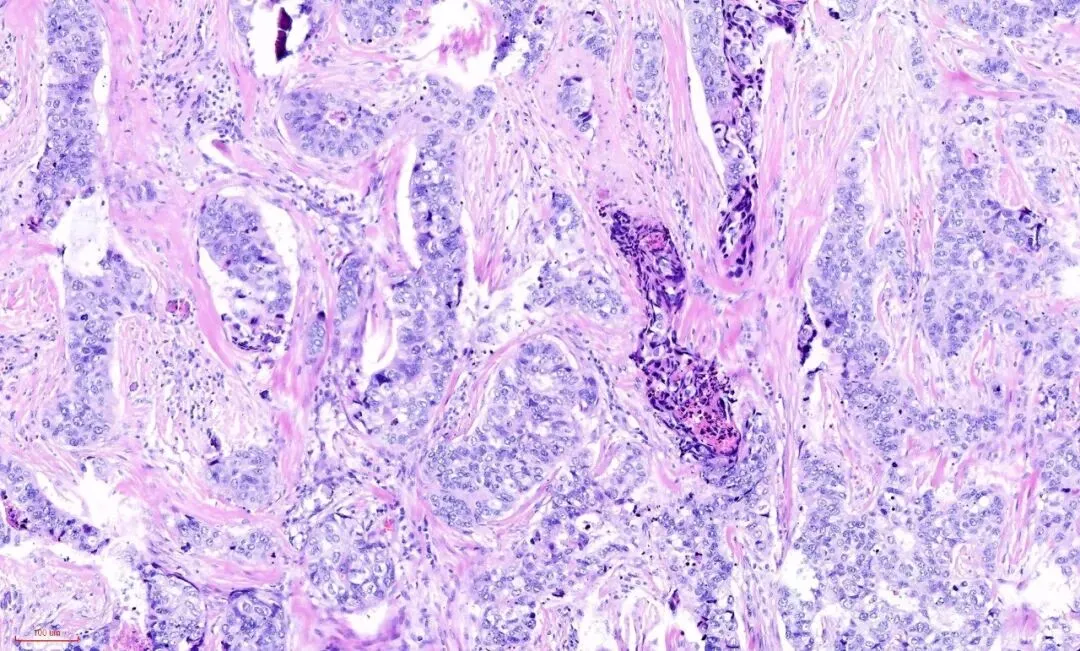

再观察腺体,可见到受挤压的腺体还保留着腺上皮(蓝染的)和肌上皮(粉染的或透明的)的双层结构。

转高倍,看到腺上皮肌上皮的双层结构,如下图:

所以,即便是这样的杂乱无章,貌似癌的浸润,也还是良性的,这时应仔细观察细胞的异型性。如果是癌,细胞异型性是很大的,如下图:癌性的间质促纤维反应,也是粉染的,但不像硬化性腺病那样去挤压腺体,而是腺体与间质之间有一些裂隙,更大的区别在于细胞异型性,常有丰富的嗜酸性胞质,有不同的核级,核从规则到多形性,核大深染,核仁明显,核分裂象易见。如下图:

五、腺上皮细胞无明显异型性:形态一致,核浆比正常。细胞核大小、形状规则,染色质均匀,核仁不明显,核分裂象罕见或缺乏。如果是癌,细胞异形性相对较大,细胞通常比较大,常有丰富的嗜酸性胞质,有不同的核级,核从规则到多形性,核大深染,核仁明显,核分裂象易见。